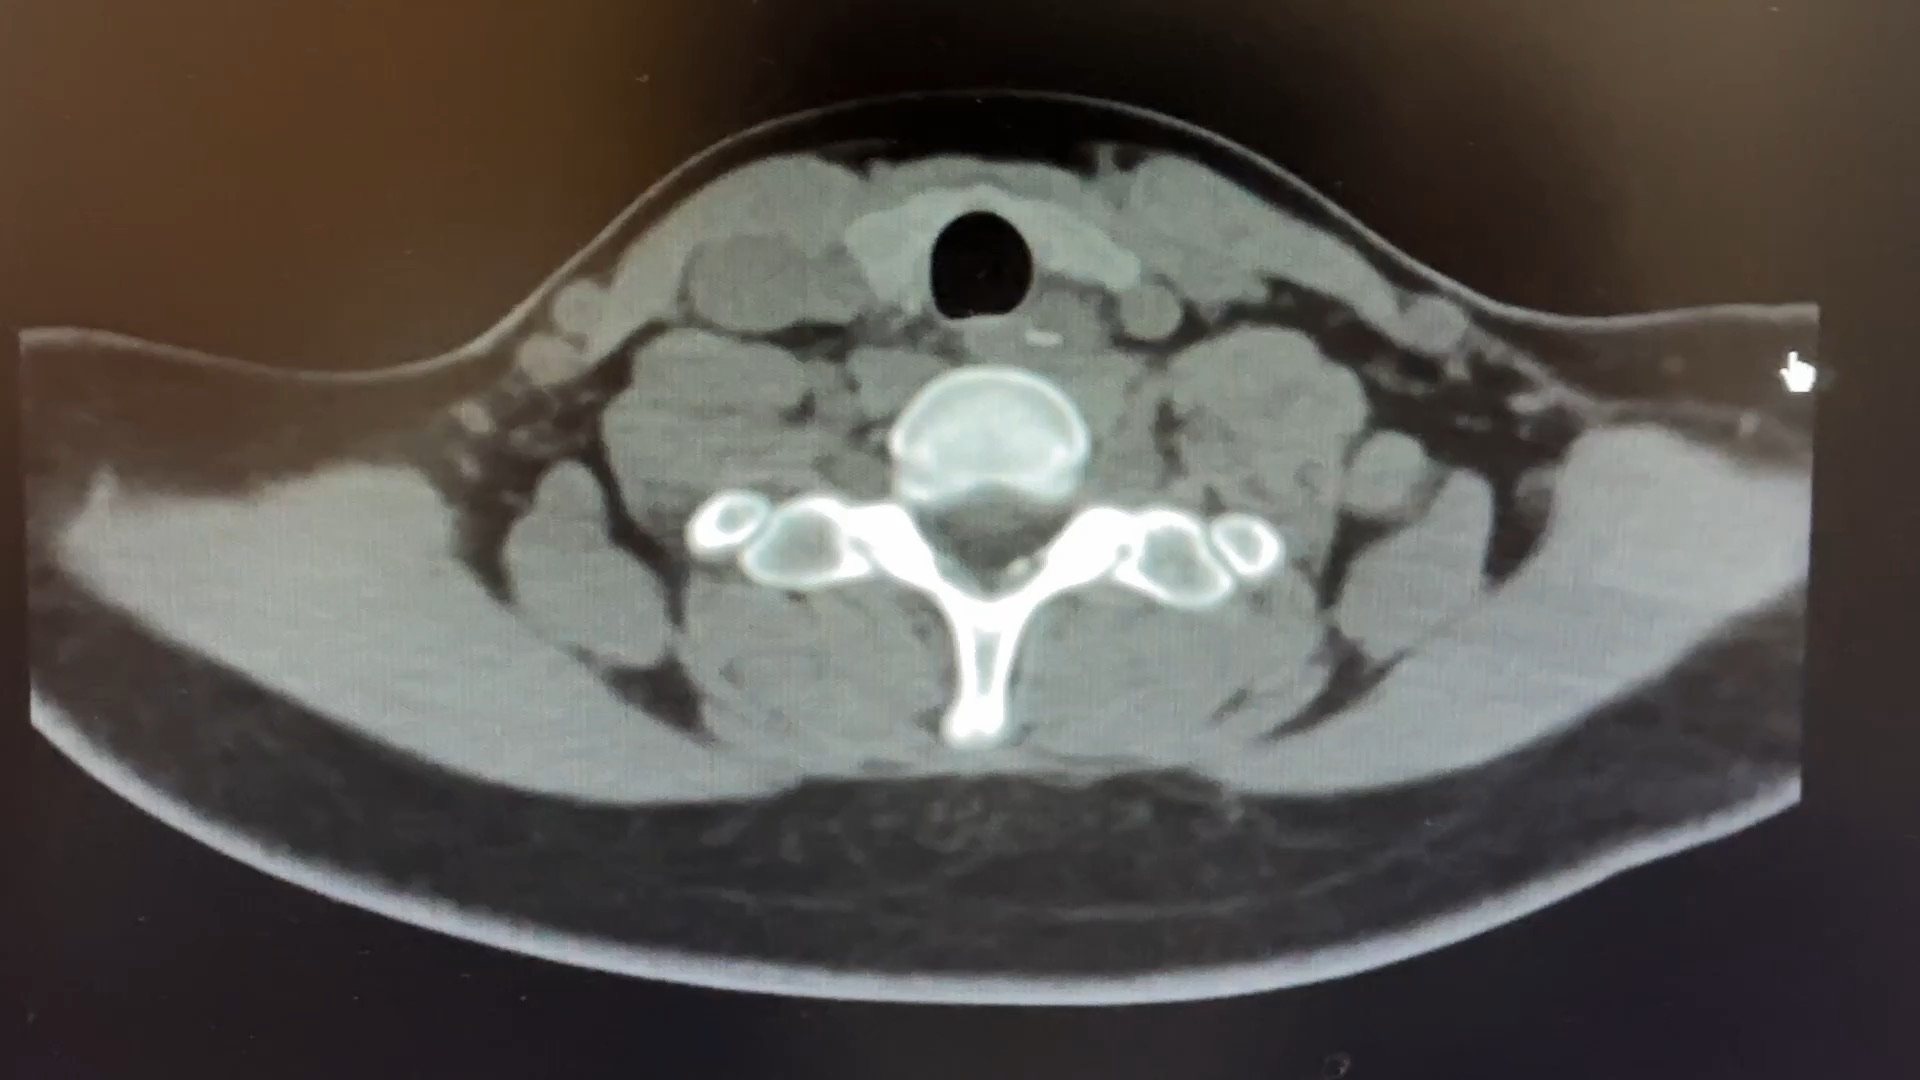

患者 女 19岁 高三学生,吃鸭肉不小心吞入🦴骨头出现异物感、胸痛1小时入院,入院后CT如下。

CT所见:食管高密度异物,有穿孔的表现,邻近血管约3mm。